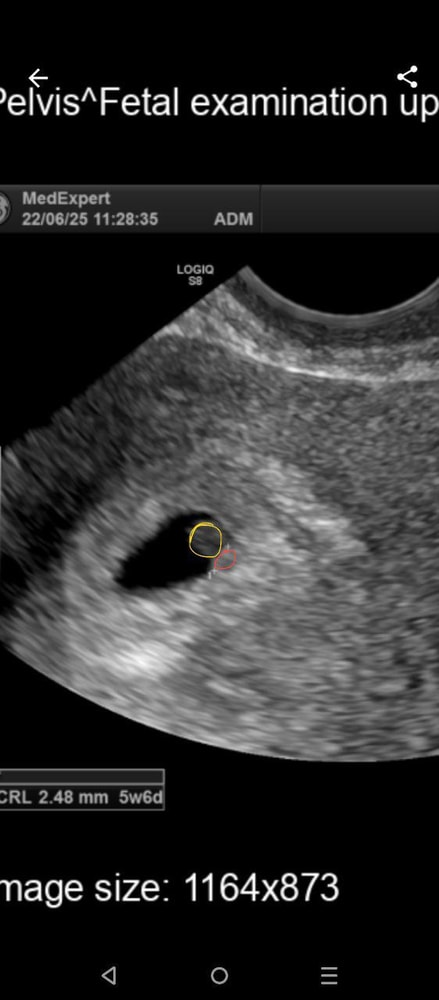

Сегодня сделала узи, вот что по узи

Плодное яйцо в матке сдв 5,6мм

Желточный мешок сдв 3,2 мм

Ктр эмбриона 2мм

Сердцебиения нет.

По узи срок 4недели.

Что-то мне не нравится маленькое плодное яйцо и большой для него желточный мешок. Опять же срок отстает очень прилично.

Очень маленькое ПЯ почему-то. У меня при 5 мм не было ещё ни жм, ни эмбриона. А тут малек 2 мм. Как он там помещается в пя с таким жм 🤔

Екатерина , ааа, ну логично, даже по картинке видно - если бы и правда пя 5,6, то жм со своим размером должен почти полностью его занимать! А там ещё два таких поместятся😆